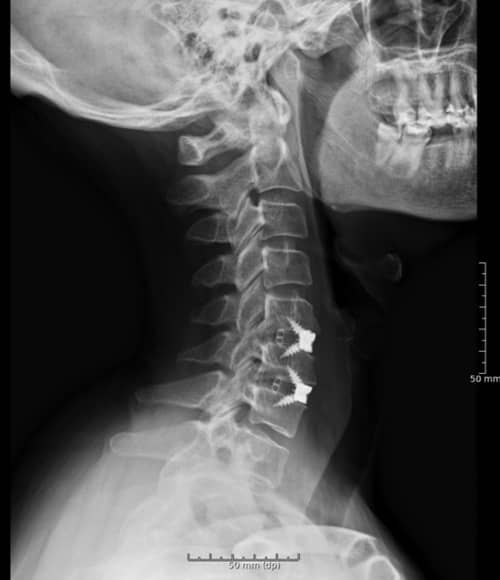

Descompresión y estabilización espinal

Entre las intervenciones quirúrgicas, la descompresión puede incluir técnicas como la laminectomía, donde se elimina parte del hueso que está ejerciendo presión sobre la médula. La estabilización se enfoca en la fusión de las vértebras para asegurar que no haya movimiento excesivo en la columna, lo que puede contribuir a la compresión de la médula espinal.

Discectomía cervical anterior

Este procedimiento implica la eliminación de un disco intervertebral dañado que está presionando sobre la médula espinal o las raíces nerviosas. Se realiza a través de una incisión en la parte anterior del cuello, lo que permite al cirujano acceder a la columna cervical y realizar la intervención de manera efectiva.